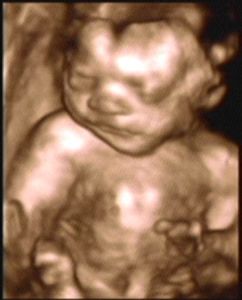

3D/4D SONOGRAPHY 18-24 WEEKS

- Normal Sonography is 2 dimensional. In 3 dimensional Sonography the information is obtained simultaneously in 3 planes (X, Y & Z).

- Highly sophisticated software reconstructs this information into a distinct 3D image.

- From a continuous 3D acquisition you get a live action view. It is known as 4D where 4th dimension is time.

- Improved identification of suspected or detected anomalies.

- More accurate identification of the extent & size of anomalies.

- Improved maternal -fetal bonding.